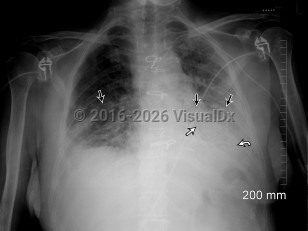

Single portable semi-upright AP view of the chest. There are bilateral airspace opacities with a predominantly lower lobe distribution, left greater than right (straight black arrows). An air bronchogram is also evident within the left lung (straight white arrow). There is a craniocaudal gradation of density which suggests pleural effusions, although this is difficult to appreciate on a semi-recumbent exam (curved white arrow). Follow-up CT confirmed bilateral pleural effusions, left greater than right.